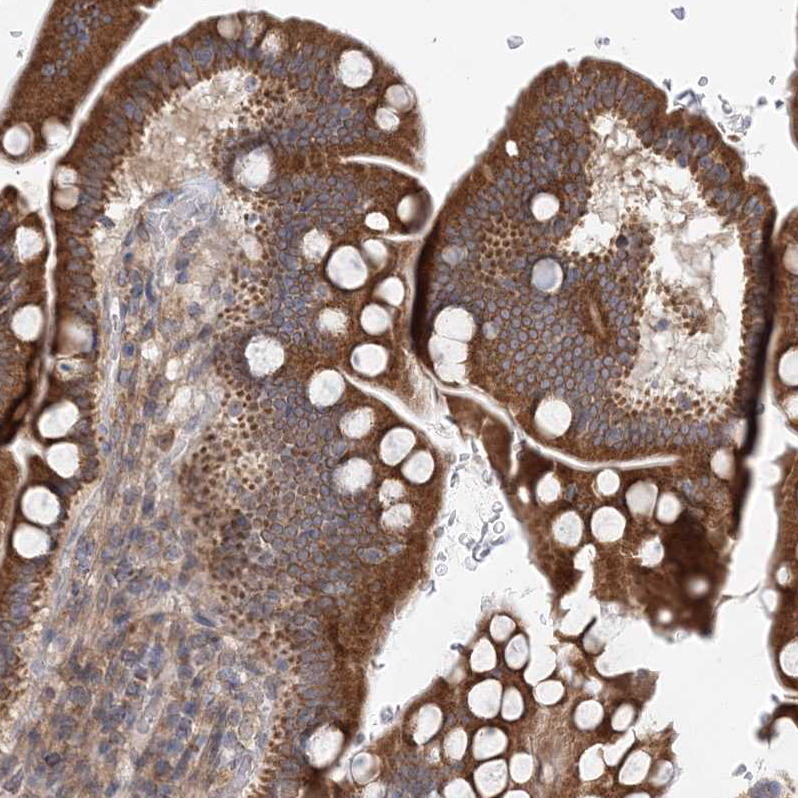

Immunohistochemical staining of human testis shows strong cytoplasmic positivity in Leydig cells and cells in seminiferous ducts.